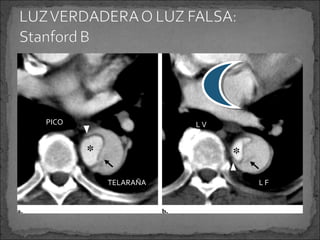

PICO

LV

TELARAÑA

LF

Ruptura de la íntima que permite el paso de la sangre hacia

la capa media, permitiendo la formación de dos luces en

el vaso, una luz verdadera y una falsa.

 Avances en tratamientos percutáneos hacen importante

distinguir entre la luz verdadera y la falsa.